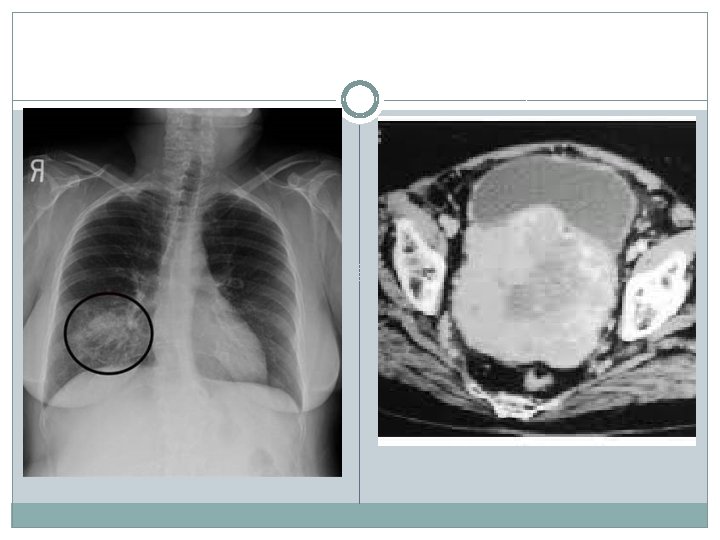

Otros métodos �Cistoscopia Identificar numero de lesiones , aspecto, tamaño y localización �Resección transuretral de vejiga (RTU-V) Diagnostico y terapéutico �Estudio de extensión TAC Rx tórax Gama óseo PFH